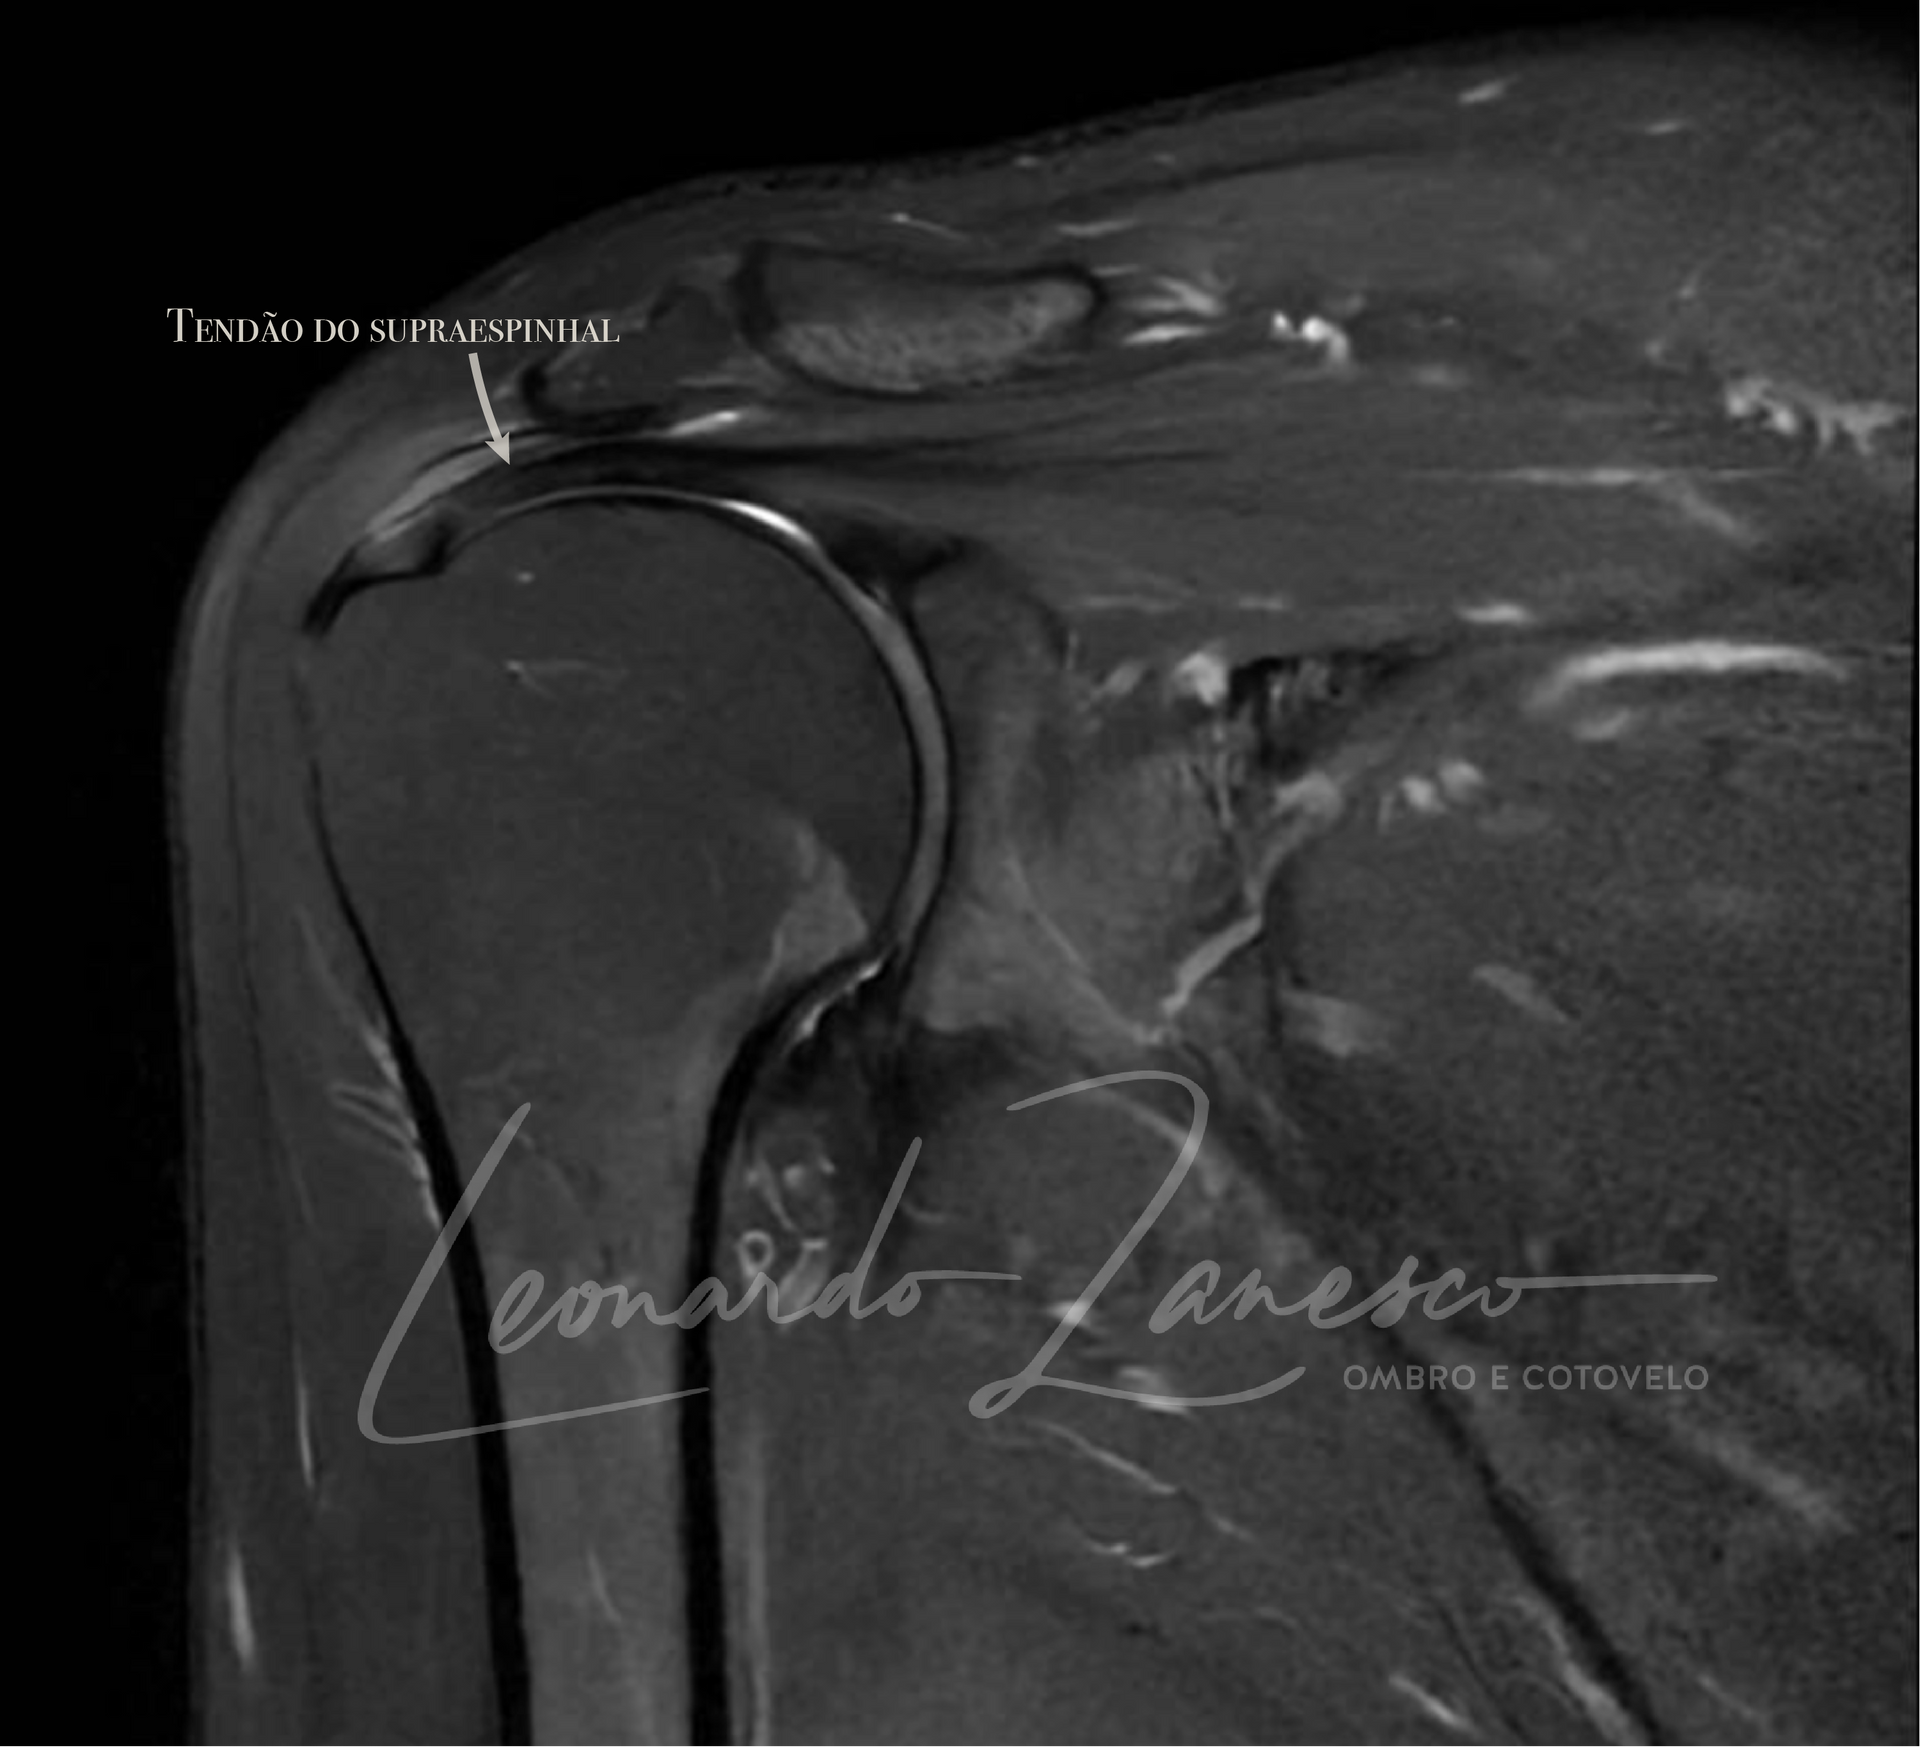

O manguito rotador é uma estrutura complexa composta por quatro músculos e seus tendões que envolvem a cabeça do úmero (o osso do braço), estabilizando a articulação do ombro. Esses músculos são essenciais para a movimentação e estabilidade do ombro, permitindo uma ampla gama de movimentos coordenados. Os músculos que compõem o manguito rotador são:

- Supraespinhal: Localizado na parte superior do ombro, este músculo é responsável por elevar o braço lateralmente. Ele é frequentemente afetado em lesões devido ao seu papel crucial na elevação do braço.

Sinais de ruptura incluem dor intensa, fraqueza significativa, limitação de movimento e estalidos no ombro. Exames de imagem como ressonância magnética (RM) confirmam o diagnóstico.